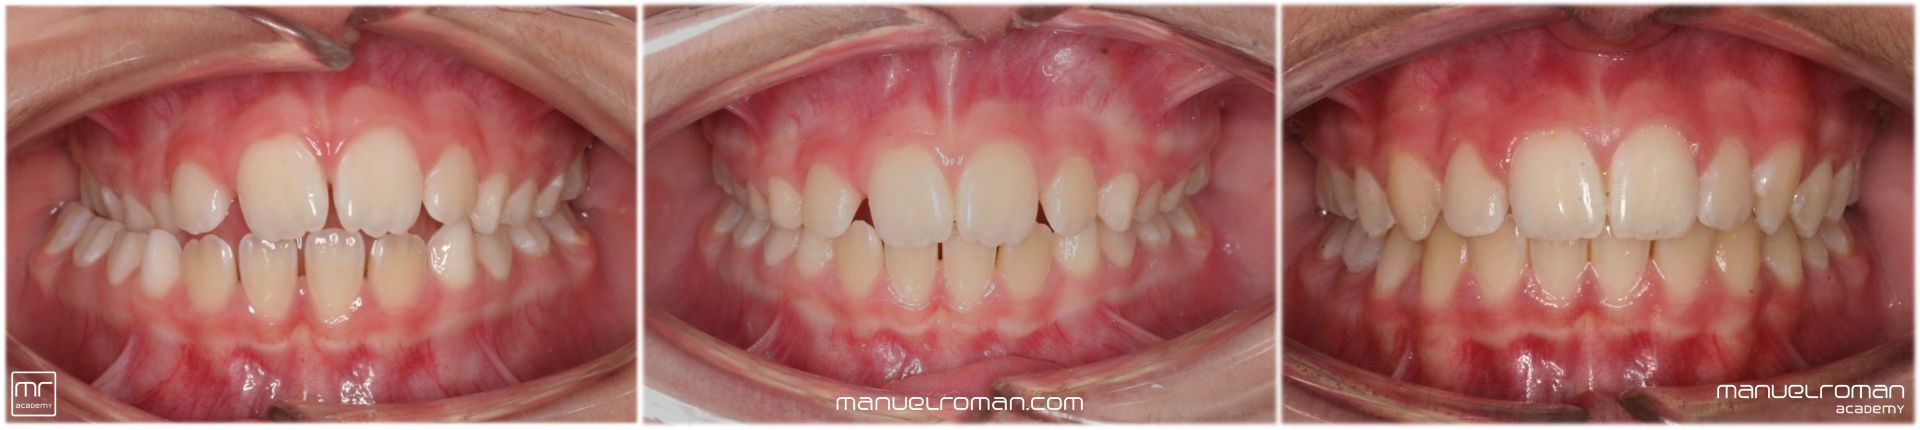

La Masterclass de ortodoncia invisible y ortopedia en niños impartida por el Dr. Manuel Román está dirigida a aquellos dentistas, odontopediatras y ortodoncistas que quieran especializarse en el tratamiento precoz, en niños y pacientes en crecimiento con alineadores.

Aprenderás a tratar pacientes desde los 4 años con ortodoncia preventiva e interceptiva hasta la adolescencia.

Serás un experto en ortopedia dentofacial, conocerás todos los secretos sobre el tratamiento de la mordida cruzada posterior y el avance mandibular en clases II (Spark, Invisalign, Angel, Twin Block, Herbst) junto con el resto de maloclusiones como tratamiento de la clase III o la mordida abierta anterior (y hábitos).

También aprenderás a resolver los problemas de erupción con los que nos encontramos en erupción mixta: dientes ectópicos, falta de espacio, desarrollo de las arcadas, transposiciones dentarias, etc. No solo veremos caninos incluidos, también incisivos, premolares y molares incluidos.